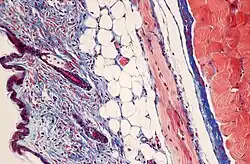

Mouse skin stained with Masson's trichrome stain.

Most recipes produce red keratin and muscle fibers, blue or green collagen and bone, light red or pink cytoplasm, and dark brown to black cell nuclei.